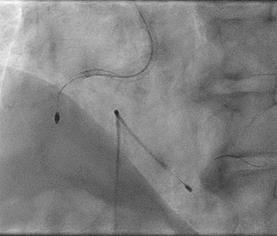

Can thiệp ngã ba động mạch liên thất trước và nhánh chéo 1 với hai stent có bọc thuốc bằng kĩ thuật cullote. Tiếp tục can thiệp động mạch vành phải với ống thông can thiệp (guiding catheter) (Cordis JR4 cm 6Fr) và dây dẫn (Asahi Sion 0.014”). Nong tổn thương bằng bóng 3.5 x 15mm (Neich Sapphire), bóng 4.0 x 12 (NC Quantum Apex), bóng cắt 3.5 x 15 (Cutting balloon, Angiosculpt) không làm vỡ được mảng vữa xơ. Quyết định dùng hệ thống khoan cắt mảng vữa xơ với dây dẫn mềm (Boston Scientific Rotablator Rotalink Plus) và mũi khoan (burr) 1.5mm. Tuy nhiên vì kích thước động mạch quá lớn nên mũi khoan đi qua tổn thương mà không chạm vào mảng vữa xơ được. Chuyển sang mũi khoan có đường kính lớn hơn 2.15mm với tốc độ khoan 150000 vòng /phút. Khi mũi khoa đi qua được 1/3 tổn thương thì không thể di chuyển được tiếp. Nhận định tại thời điểm đó là mũi khoan bị kẹt trong tổn thương tại đoạn giữa của động mạch vành phải. Ngay lập tức các bác sỹ có kinh  nghiệm can thiệp trong bệnh viện được mời đến phòng can thiệp đồng thời thông báo cho các phẫu thuật viên tim mạch chuẩn bị trong trường hợp cần thiết. Bệnh nhân có biểu hiện đau tức ngực trái, tuy nhiên mạch và huyết áp tương đối ổn định, điện tim không thay đổi. Dòng chảy trong động mạch vành còn duy trì nhưng chậm TIMI 2. Sau khi hội ý, hướng xử trí đầu tiên là dùng dây dẫn cứng Conquest Pro (Asahi) để đi qua tổn thương nhưng không thành công. Sau đó chúng tôi quyết định cắt đoạn đầu của hệ thống nối mũi khoan, đưa ống thông heartrail (Terumo) sát vào mũi khoan nhằm thay đổi tư thế và cố định mũi khoan vào dây dẫn để đưa ra ngoài. Cuối cùng mũi khoan được đưa ra ngoài thành công. Tổn thương tiếp tục được nong bằng bóng cắt và bóng áp lực cao và đặt được giá đỡ kim loại (stent) bọc thuốc 4.0 x 26mm. Kết quả là động mạch vành được mở rộng hoàn toàn, bệnh nhân không còn đau ngực, huyết động ổn định.

Hình 2: A- đường dẫn của mũi khoan được cắt bằng kéo; B – đưa ống thông Heartrail vào sát mũi khoan; C – toàn bộ hệ thống được đồng thời đưa ra ngoài; D – hình ảnh sau đặt stent.